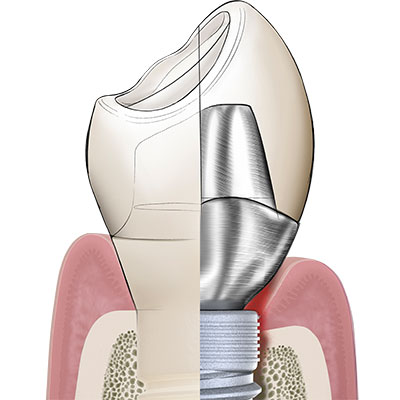

Patent™ has a soft-tissue-level design that positions the crown margin at the equigingival level.

Among other things, Rompen argues that tissue-level designs are advantageous over bone-level designs with bacteria-prone microgaps at the subgingival level. Having a soft-tissue-level design, the Patent™ Implant neither incorporates a microgap at the subgingival level nor at the level of the crestal bone. Its crown seat and the implant platform, in which the glass fiber core build-up is cemented, are instead positioned at the equigingival level. As a result, the crown margin of the final restoration is easily accessible and easy to clean, which greatly reduces the risk of bacteria-induced inflammation of the peri-implant soft- and hard tissues.

In its endosseous portion the Patent™ Implant has a threaded part with an ideal surface roughness of approximately Ra 5,7 µm that extends into a threadless (“thread-off”) part above it. A 2.5 mm tall tulip-shaped transgingival collar rises from the implant body. This portion of the implant is machined and does not undergo any surface treatment after milling to allow optimum soft-tissue adhesion. From this transgingival tulip emerges a partial abutment (the ferrule) which incorporates the 3.3 mm deep 3C™ connection at its center.

Dentists worldwide are familiar with the concept of a ferrule within the context of endodontic treatment: In order to provide an endodontically treated tooth with fracture resistance and its crown with stability, a portion of the upper part of the tooth is prepared into a ferrule, in which the post and core are inserted. The integrated partial abutment of the two-piece Patent™ Implant is the equivalent of a ferrule on an endodontically treated tooth. The ferrule of the Patent™ Implant is typically supragingival, because it is always incorporated inside the body of the crown. The ferrule incorporates the 3C implant connection at its center, in which the glass fiber post is cemented. Once cemented, the post is prepared using a high-speed diamond drill – just like any post would be prepared in endodontic dentistry. The glass fiber post, having dentinlike properties, is able to attenuate the masticatory forces within the context of the definitive restoration in a favorable way. Once cemented and prepared to form, the post is restored with a crown or any other kind of definitive prosthesis. Once could say that Patent™ is a one-piece implant which gives you the flexibility of a two-piece implant.to them.

The correct implant position

If the Patent™ Implant is placed correctly according to the manufacturer’s surgical protocol (and not inserted too deeply), the interface between the crown margin and the implant table is at the equigingival level and the ferrule with the 3C implant connection at its center is at the supragingival level. Without there being a bacteria-prone subgingival microgap, the peri-implant soft tissues can begin to adhere firmly to the transgingival tulip in the form of a cuff shortly after insertion, largely free of irritation and undisturbed by bacterial pathogens. Because of this so-called “early sealing” of the mucosa to the transgingival implant portion, the risk of subgingival cement residues or glass fiber components (as a result of the intraoral cementation process) is virtually non-existent.to them.